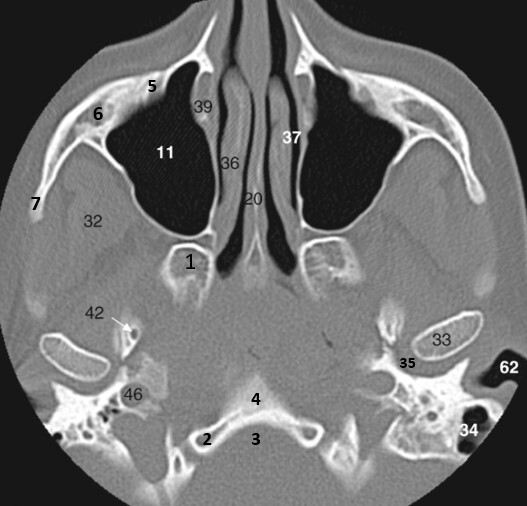

6

Label 7-12

A

7=Crista Galli (Ethmoid)

8.=Hard palate (Maxilla)

9=Rt. Maxillary sinus

10=Nasal septum

11=Rt. Inferior nasal concha

12=Rt. Middle nasal concha

9

Label 8,9,10,12,13,18

8=Hard palate (Maxilla)

9=Lt maxillary sinus

12= Rt. Middle nasal concha

13=Rt. Superior nasal concha

18=Rt. Ethmoid air cells